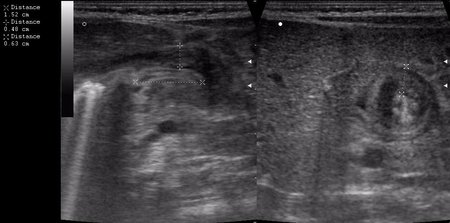

а у нас сегодня опять одна красава! (месяца 3 НИОДНОГО пилоростеноза небыло!)

сорри, колесико недотянула

Признак "пончика".

А что, похоже.